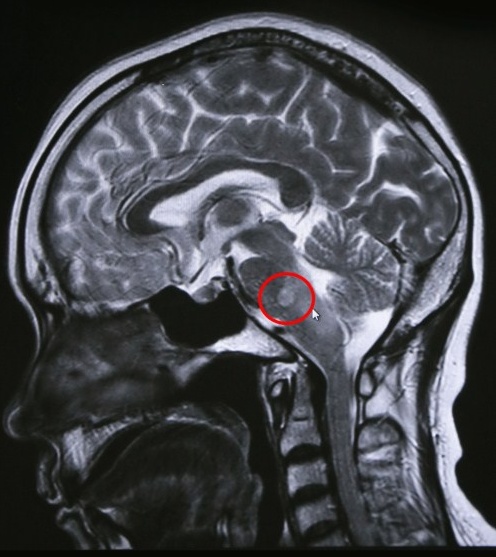

說起孫主任的“科技眼”,給他看過片子的病人們都記憶深刻,不少病人說:“孫醫(yī)生的眼睛,挽救了我的一條性命。”這雙眼睛,使數(shù)不清的患者避免了不必要的手術(shù),也使數(shù)不清的患者能在疾病的萌芽階段及早治療診斷,得到及時(shí)治療,避免了大手術(shù)。南通的一位患者在多家三甲大醫(yī)院檢查,都說他得了腦部腫瘤要做手術(shù),后來,在藍(lán)十字腦科醫(yī)院做了MR,經(jīng)認(rèn)真仔細(xì)的讀片后,孫海輝主任認(rèn)為這是炎性病變,不是腫瘤,只要藥物保守治療即可,病人免了開刀之痛苦,對孫主任千恩萬謝。

腦干炎性病變非腫瘤